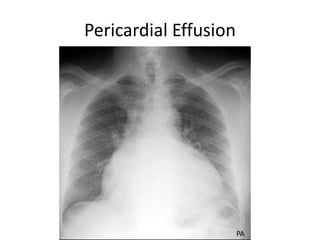

Pericardial Effusion

• Pericardial effusion causes an enlarged heart shadow that is

often globular shaped (transverse diameter is

disproportionately increased).

• A "fat pad" sign, a soft tissue stripe wider than 2mm between

the epicardial fat and the anterior mediastinal fat can be seen

anterior to the heart on a lateral view.

• Serial films can be helpful in the diagnosis especially if rapid

changes in the size of the heart shadow are observed.

Approximately 400-500 ml of fluid must be in the pericardium

to lead to a detectable change in the size of the heart shadow

on PA CXR.

PA